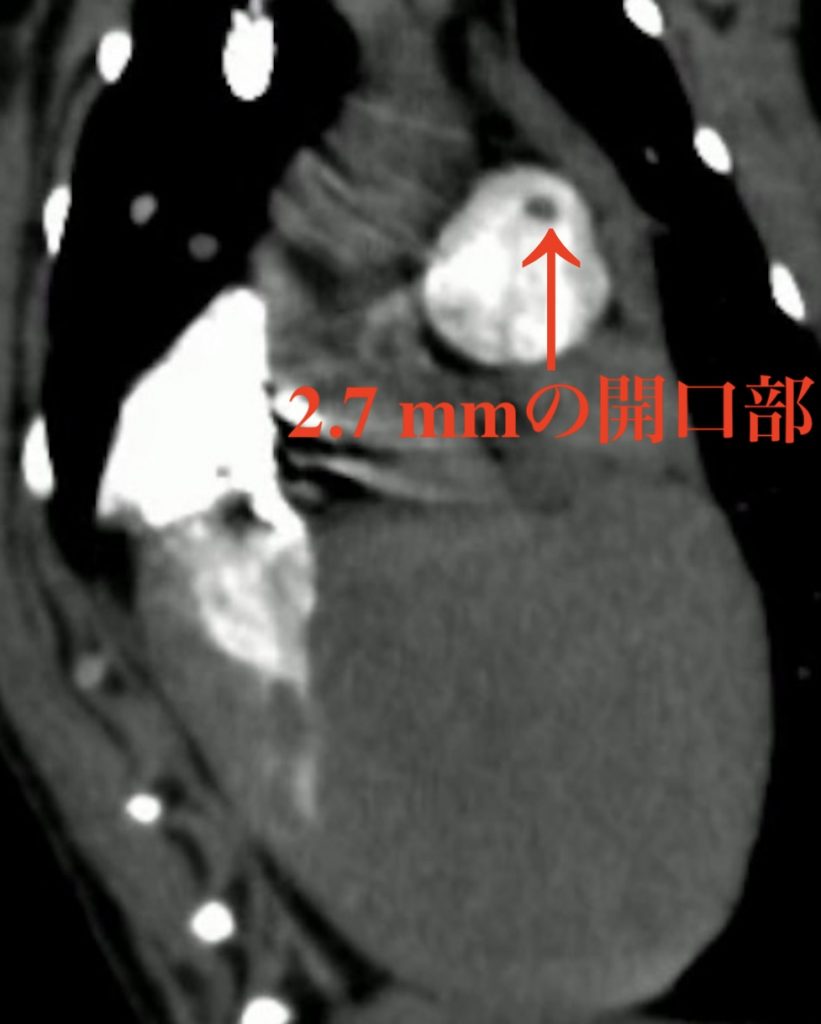

そこで竹田らはContinuous HIgh-Enhanced COntrast (CHIECO)心電同期CT造影検査法を開発し、直径2.7 mmの僅かな開口部を明瞭に描出することに成功しました。この手法はまだ改良の余地はあるものの、これまで明瞭に撮影できなかった小型犬や猫などの先天性心疾患をより正確に評価可能になることが期待されます。